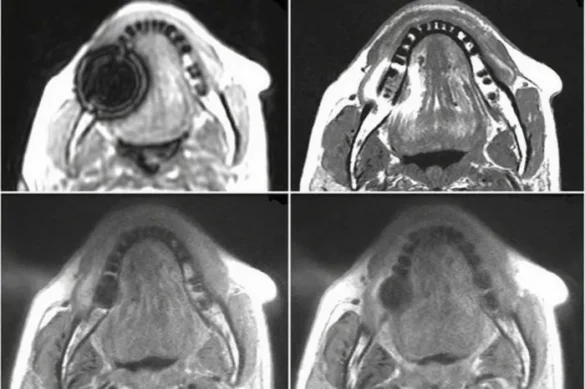

Will Dental Implants Affect the Quality of My MRI?

In general, dental implants do not prevent you from having an MRI. However, it is possible for implants to create a small image distortion, known as an artifact, on the MRI. This is more likely if the scan focuses on the head, jaw, or neck regions near the implant. Artifacts appear as blurry or distorted spots on the images, and can occasionally make it harder for the radiologist to see fine details in that area.

- If your MRI is focused on the jaw, sinuses, or brain, discuss with your radiologist what to expect. In rare cases, other imaging methods such as CT scans or X-rays might be advised for a clearer view of the area near your implant.